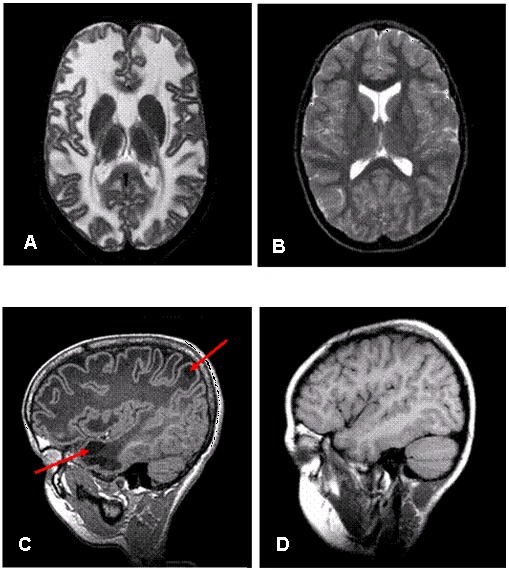

头颅MRI具有诊断性意义。(见图 1

Figure 1. . Brain images of an individual with MLC (A, C) and an unaffected individual (B, D) A.

MLC患儿头颅(A,C)及正常个体MRI图(B,D)。A.9岁MLC患儿T2加权像,可见弥漫性异常信号及白质轻度肿胀。B.正常个体T2加权像 (more...)

• 大脑半球白质弥漫性异常信号及轻度肿胀;见图 1A(MLC1型患者),图 1B(正常个体)

• 中央白质结构,包括胼胝体、内囊和脑干虽然会受累,但较其他结构保存较好。

• 小脑白质常有轻度异常信号,但不伴肿胀。

• 几乎所有患儿均有皮层下囊肿,可出现在前颞叶,但更多的是在额顶叶。见图1C(MLC1型患儿),图1D(正常个体)

• 随着病程进展,白质肿胀减轻,开始出现大脑萎缩。皮层下囊肿数量及体积均增加。在部分患儿中,囊肿体积增致巨大,占据大量额顶叶白质位置。而另外一些患儿,大脑白质异常逐渐消失,大脑白质异常信号强度较前减弱。

• 弥散加权像(Diffusion-weighted imaging,DWI)上异常白质弥散增强[Itoh et al 2006, van der Voorn et al 2006]。

• MLC2B型患儿1岁以内的MRI同上所述,但随后明显好转。部分患儿MRI可在数年内恢复正常,但部分患儿可遗留微小的额叶、颞叶皮层下白质异常以及前颞叶的囊肿。